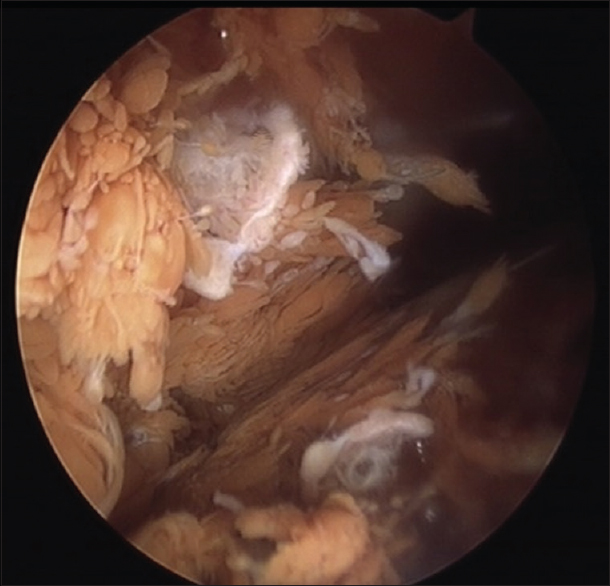

CHƯƠNG TRÌNH PHỤC HỒI CHỨC NĂNG SAU PHẪU THUẬT RÁCH SỤN CHÊM